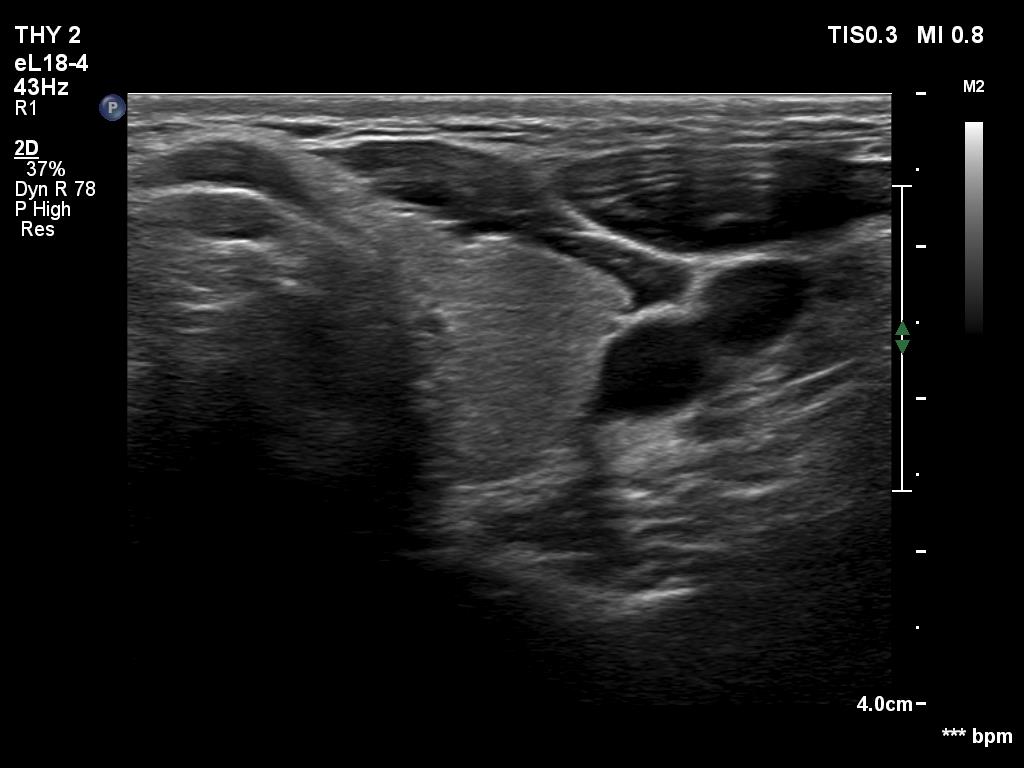

Right lobe, longitudinal scan